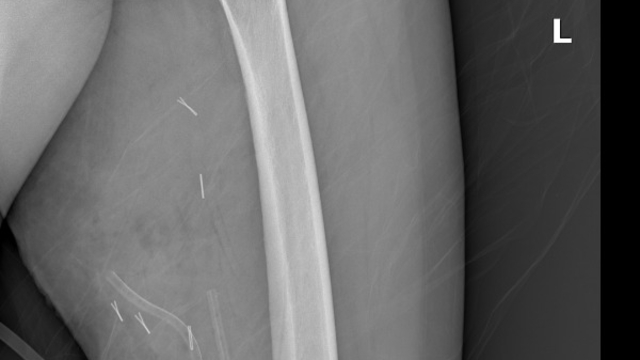

Mardin’de yaşayan H.T. (42), 3 yıl önce sağ baldırının arka kısmında oluşan ve başlangıçta yumurta büyüklüğünde olan kitlenin zamanla büyümesi üzerine Dicle Üniversitesi Tıp Fakültesi Hastanesi Ortopedi ve Travmatoloji Bölümü’ne başvurdu. Muayenede yumuşak doku kitlesi olduğu değerlendirilen şişliğin alınması için Ortopedi ve Travmatoloji Anabilim Dalı Öğretim Üyesi Prof. Dr. Emin Özkul ve ekibi tarafından ameliyat kararı verildi. Yaklaşık 2 saat süren operasyonla kitlenin çıkarıldığı, kitlenin 5 kilo 668 gram geldiği belirtildi.

Prof. Dr. Emin Özkul, vücutta görülen kitlelere büyümeden müdahale edilmesi gerektiğini ifade ederek, “Hastamız 42 yaşında bir kadın. Komşu şehir Mardin’den geldi. Bölge hastanesi olduğumuz için bu tür hastalar Mardin’den, Şırnak’tan ve diğer illerden çok geliyor. Bu hastalara önerimiz; ‘küçük bir kitle, ağrısız bir kitlem var, ele gelen bir şişliğim var ama bunda ağrı olmadığı için herhangi bir şey olmaz’ dememeli. En yakın sağlık kuruluşuna başvurup en azından kitlenin bir öneminin olup olmadığını teyit edilmesi, bir uzman tarafından bunun doğrulanmasını istiyoruz. Bu hasta da 3 yıl önce fark edilmiş küçük bir kitle, zamanla çok büyük boyutlara, yaklaşık 6 kiloya varan boyutlara varmıştı. Neredeyse bütün bacak boyu yayılan bir kitlesi mevcuttu. Bu kadar büyümenin şöyle sıkıntıları oluyor, kişinin bacağında, kolunda fonksiyon kaybına, yeri geliyor ekstremite kaybına, yani bacağını kaybetmesine yol açabilecek sıkıntılara yol açıyor. Küçükken bunlarla baş etmek daha kolay. Kişinin ekstremitesinde, bacağında, kolunda bir sıkıntı yaratmadan bunları telafi etmek, bunları alıp çıkartmak, ameliyatla bunları tedavi etmek daha kolayken bu boyutlara vardığında kişinin bacağında, kolunda fonksiyon kaybı, sakatlık riski çok yüksek oluyor. Bu sebeple küçükken önleminin alınmasında yarar var” dedi.

Kitlelerin görülmesi halinde sağlık kuruluşlarına başvurulması gerektiğini belirten Prof. Dr. Özkul, “Hastamızda yaklaşık olarak 3 yıl önce şikayetleri başlamış. Sonra zaman içerisinde hızla büyüyen bir kitleye sahipti. Şanslıydı ki herhangi bir sinirine zarar vermemişti. Hayatına fonksiyon bozukluğu olmadan devam edebilecek. Bölgemize yaşayan ve ülkemizde yaşayan herkese şunu söylüyoruz. Küçük de olsa yumuşak doku kitlelerini önemsemeleri ve uzman görüşü almalarını öneriyorum. Bu hastadan 5 kilo 668 gramlık bir kitle çıkarttık. Bu benim mesleki yaşamım boyunca çıkarttığım en büyük kitlelerden bir tanesiydi. Biraz daha büyük boyutlara varmış olsa kişinin bacağını kurtarma şansınız olmuyor. Bu sebeple bunlara dikkat etmek gerekiyor. Hızlı büyüyen bir kitleniz var ise, ağrısız da olsa mutlaka ve mutlaka tedavi için en yakın sağlık kuruluşuna veya bizim üniversitemizin polikliniklerine başvurabilirsiniz” diye konuştu.